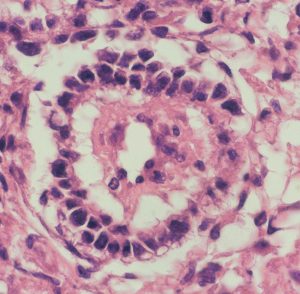

組織学的には,円柱様ないし楕円形の上皮様細胞の網状配列構造を示す腫瘍であり,一部にSchiller-Dubal bodyと呼ばれる血管周囲に集族する特徴的な細胞配列が見られます。これは,一層あるいは多層の上皮様細胞が,中心となる血管をやや離れて取り囲むように並ぶ構造です。また,PAS陽性の好酸性球状体が見られAFPが強陽性となります

視床下部に発生したchoriocarcinomaの病理像(左からHE染色, HCG染色, PLAP染色):腫瘍の大部分にHCG陽性細胞が認められますが,一部ではPLAP陽性のgerminoma細胞様の腫瘍細胞も散見されます。